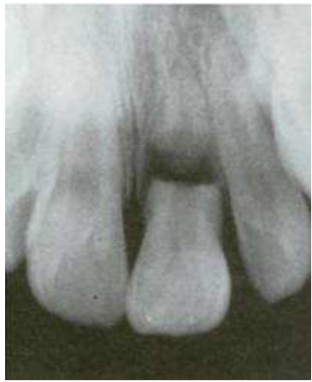

36. 如下圖所示,外傷造成門牙牙根5 mm寬之斷裂,最佳處置為何?

(A)拔除該牙,再觀察 (B)將該牙作冠髓切除術,再固定觀察 (C)將該牙作牙髓切除術,再固定觀察 (D)將該牙牙冠復位固定,再觀察